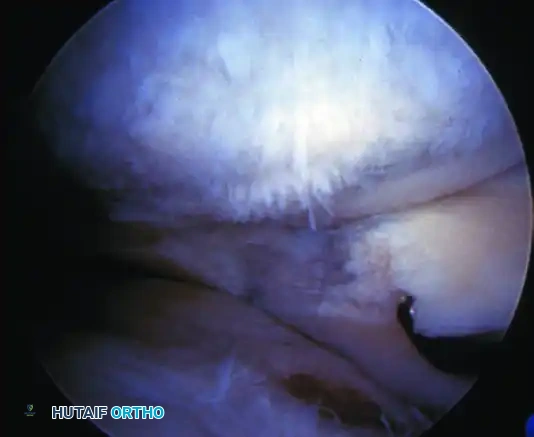

Patellofemoral pathology frequently coexists with ligamentous instability or presents as an isolated source of anterior knee pain. "Chondromalacia" refers specifically to the pathological softening, fibrillation, and degradation of the articular cartilage of the patella.

Arthroscopic evaluation of chondromalacia is graded to guide treatment:

- Grade I: Softening and swelling (blistering) of the articular cartilage.

- Grade II: Fragmentation and fissuring confined to an area ≤ 0.5 inches in diameter.

- Grade III: Severe fragmentation and fissuring involving an area > 0.5 inches in diameter (often described as a "crabmeat" appearance).

- Grade IV: Full-thickness erosion of cartilage down to exposed subchondral bone.

For isolated Grade II or early Grade III chondromalacia without significant malalignment, arthroscopic mechanical débridement (chondroplasty) to stabilize unstable cartilage flaps is often sufficient.